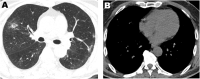

The purpose of this case report is to describe the imaging and associated clinical features of an asymptomatic novel coronavirus pneumonia (COVID-19) patient outside Wuhan, China. The principle findings are that in this patient with laboratory-confirmed COVID-19, CT findings preceded symptoms and included bilateral pleural effusions, previously not reported in association with COVID-19. The role of this case report is promotion of potential recognition amongst radiologists of this new disease, which has been declared a global health emergency by the World Health Organization (WHO).